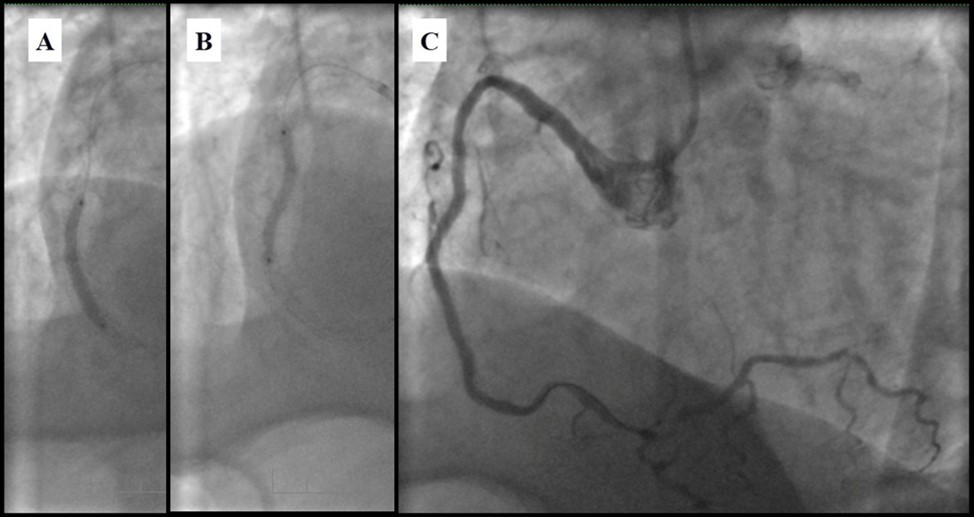

Due to financial problems the second stage was performed after 3 months (during this time the patient solved his financial problems). CAG revealed patent stents in LAD (Figure 7), and 60-70% restenosis by BMS in RCA (Figure 8). In-stent restenosis was treated by plain old balloon angioplasty (POBA), the optimal result was obtained (Figure 9). After LMCA quadrifurcation balloon predilation, 2.5×26 mm DES (Resolute Integrity, Medtronic) was implanted in the IMA, using a modified balloon mini-crush technique. The stent was minimally protruded in the LMCA and its edge was crushed by preloaded MB balloon. Next 2.5×30 mm DES (Resolute Integrity, Medtronic) was implanted in OM1 through the CX (first marginal and circumflex arteries in this particular case have the same ostium). The stent was protruded in the LMCA as in conventional modified balloon crush stenting technique, after stent deployment, its balloon was pulled back and overinflated, then protruded stent was crushed by preloaded MB balloon (Figure 10). 3.5×15 mm DES was implanted in the LMCA so that distal part of the stent covered ostial and proximal segments of the LAD. Sequential post-dilatations were performed using a kissing balloon technique (1. LMCA-LAD-IMA,2. LMCA-LAD-CX-1OM). After post-dilatations, through the stent implanted in CX-OM1, coronary wire and smaller diameter balloon (2.0 mm) were advanced in direction of the CX mid-segment and by balloon dilatation stent’s strut was opened (provisional stenting technique for CX). Finally, the proximal optimization technique was performed in the LMCA using a 3.5 mm diameter non-compliant balloon (Figure 11). The final angiographic image was good, the intervention ended without complications (Figure 11, Figure 12). We could not confirm the result with IVUS or OCT due to several technical and financial problems (not covered by insurance). 1 month after PCI, at regular checkout, the ejection fraction was 48%, the functional class of the Congestive Heart Failure decreased from class II-III to class I and the patient complaints have been disappeared.

Figure 7.Patent stents in LAD; A – AP-cranial 30° projection, B – Right anterior oblique 20°/caudal 20° projection.

Figure 9.RCA; A, B - Plain old balloon angioplasty; C - Angiography result.